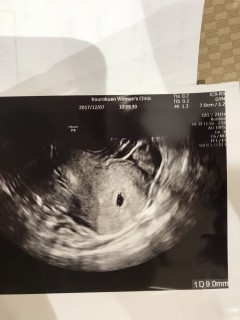

今日胎嚢確認出来ました~! 泣きそうなくらい嬉しかったです、まずは第一段階クリアって感じかな? ただもともと卵巣が腫れていたので大きい黒いのが見えます笑 妊娠初期は腫れてない人でも腫れることがあるそうなので心配いらないそうです。 胎嚢は1.72cm すべてが不順なので胎嚢の大きさからの仮定週数は5w2d もうこの時期から予定日が出るのには驚きました